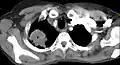

Um tumor de Pancoast é um tumor do ápice pulmonar, ou seja, um tipo de câncer de pulmão definido principalmente pela sua localização situada no topo do pulmão esquerdo ou direito. É tipicamente associado a um histórico de tabagismo.